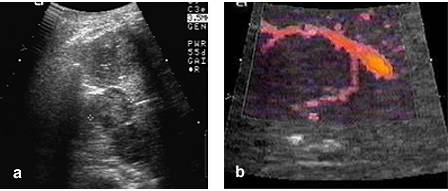

Hepatocarcinom forma encefaloida: a. tumora solida in lobul drept; b. hipervascularizatie intratumorala (reconstructie 3D); c. tumora hipo - izoecogena in lobul drept (sageata); d. scintigrafia hepatica (sageata)

Aspectul ecografic al hepatocarcinomului este variabil, in functie de caracterele sale macroscopice. Hepatocarcinomul encefaloid se prezinta ca o formatiune cu consistenta parenchimatoasa, cu dimensiuni peste 3 - 5 cm. In peste 60% din cazuri, localizarea este la nivelul lobului hepatic drept. Delimitarea tumorala poate sa fie neta, incapsulata sau poate sa fie realizata printr-un 'halou' peritumoral. Adesea, delimitarea HCC este imprecisa, ceea ce face ca aprecierea reala a dimensiunilor tumorale sa fie dificila. Fara a avea o valoare diagnostica absoluta, si atunci cand exista, haloul peritumoral, are doua calitati: sugereaza existenta unei tumori hepatice maligne si trebuie evitat in cursul biopsiei hepatice, fiind alcatuit cel mai adesea din parenchim hepatic normal. Structura HCC este, in majoritatea cazurilor, neomogena - expresie a necrozelor, a sangerarilor si a hipervascularizatiei intratumorale.

Nu exista o relatie intre structura ecografica a tumorii si gradul de diferentiere. Structura omogena a HCC se intalneste rar si, atunci cand exista, poate impune diagnosticul diferential cu angiomul hepatic, cu metastazele hepatice precum si cu chistul hidatic hepatic organizat solid. In situatii mai rare, HCC encefaloid poate sa fie omogen si izoecogen. In aceste conditii, identificarea tumorii este dificila (fig. c) si trebuiesc luate in considerare elemente ecografice indirecte, in principal dislocarile si invaziile vasculare. In acelasi timp, sunt necesare investigatii suplimentare, in principal scintigrafice (fig. d) si CT. Uneori, tumora invadeaza caile biliare mici. In aceste conditii, se pot identifica dilatari de cai biliare care schiteaza semnul 'tevii de pusca de vanatoare'. Hepatocarcinomul multicentric apare sub forma de noduli numerosi, cu dimensiuni variabile, cu consistenta parenchimatoasa. Dispersia nodulilor este neomogena, existand frecvent un nodul mai voluminos care poate constitui sursa primara tumorala. Diagnosticul diferential cu metastazele hepatice este dificil (fig. a).